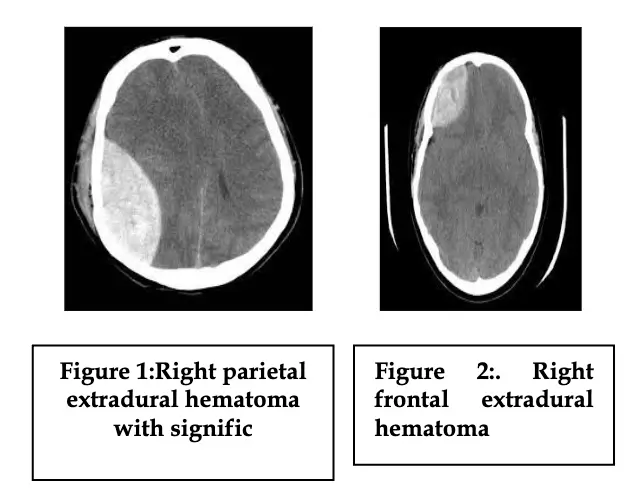

Sixty adult patients with history of road traffic accident with extradural hematoma on axial images of CT scan brain were included. All patients were allocated into three groups with 20 patients in each group. Patients in Group I were those in whom time from the occurrence of trauma to the surgical evacuation of hematoma was < 1 hour, 1 to 6 hours in group II and > 6 hours in group III.

Accumulation of blood in the potential space between dura and bone is called extradural hematoma. Extradural hematomas have threeclassical presentation. First, brief post-traumatic loss of consciousness. Secons,alucid interval for several hours. Third,obtundation, contralateral hemiparesis, ipsilateral pupillary dilatation.1,2 The commonest mechanisms of injury are an accident involving a motorbike and a fall from height.3,4Extradural hematoma of the temporal region is the most common site of supra-tentorial extradural bleeding; other locations are considered atypical.5Traumatic extradural hematoma is a neurosurgical emergency and timely surgical intervention for significant extradural hematoma is the standard treatment.6The most significant factors influencing outcome in our patients are Glasgow Coma score or consciousness level on admission, age, and associated intradural lesions and also time taken in evacuation of hematoma due to transfer of patient to neurosurgical unit. 7,8Patients who present early after road traffic accidents and with good GCS (13-15) have favorable outcome in 87% and unfavorable outcome in 9%. Time taken is defined as the time from the occurrence of trauma to the surgical evacuation of hematoma.9,10Mortality and long-term morbidity are low with early diagnosis and prompt treatment.11,12Clinical deterioration is quick, especially in posterior fossa to become fatal in most of patients with extradural hematoma so surgery can be life saving when performed in a timely manner.13-16It is generally perceived that patients with extradural hematoma present late either because of ignorance, negligence or lack of facilities in the vicinity.17,18

This descriptive study was carried out in Department of Neurosurgery, Pakistan Institute of Medical Sciences, Islamabad, for six months. It included sixty cases of extradural hematoma(sample size was calculated using WHO sample size calculator keeping level of significance 5%,anticipated population proportion(P1: 87%)1,absolute precision required:10%). Favourable outcome was defined as ability to carry on normal activity and to work; no special care needed. Unfavourable outcome was defined as inability to care for self; requires equivalent of institutional or hospital care. Inclusion criteria was all the patients with age from 15-45 years,patients of either gender,size of hematoma more than 20 ml.(calculated by the scale on axial images of CT scan brain) and only those cases of EDH with H/O road traffic accident regardless of GCS score.Exclusion criteria was age under 15 years or more than 45 years, size less than 20 ml when patient isstable,spinal extradural hematoma(because only head injured patients are included in study),extradural hematoma with evidence of diffuse axonal injury, subdural hematoma or brain contusions and those cases of EDH with H/O fall or assault. Patients were enrolled from Neurosurgery Department of Pakistan Institute of Medical Sciences Islamabad. All patients were allocated into three groups with 20 patients in each group. Patients in-group I were those in whom time from the occurrence of trauma to the surgicalevacuation of hematoma was < 1 hour, 1 to 6 hours in group II and > 6 hours in group III. Their GCS recorded. Patients matched for GCS in each group into mild (GCS: 13-15) moderate (GCS:9-12) and severe(GCS:3-8) head injury on the basis of GCS score . Final outcome assessed at 03 months of follow up for the favourableand unfavourableoutcome. Follow up was ensured through telephone contact. Chi square test was used to compare the impact of time taken on surgical outcome in 03 groups. P value < 0.05 considered significant.